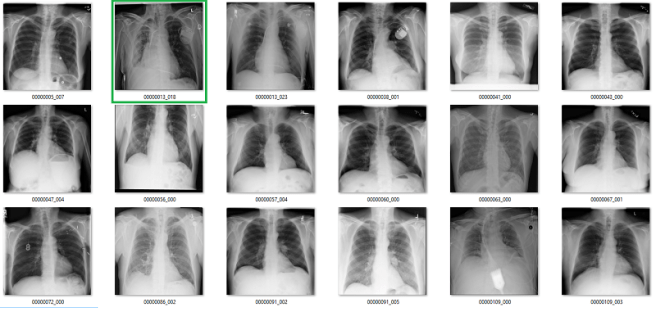

Fibrosis

We already saw above that the fibrosis labels are low accuracy, even being generous. But again, the problem is worse. In this image, the reds are incorrect labels, but the orange labels are where I have no idea. There are pleural effusions and/or consolidation. Could there be fibrosis under that? Sure, but there is no way to tell on these pictures.

Complete nonsense as far as I can tell. Below are the model predictions, compared against the labels in the dataset. Again, the same technique as earlier for picking images. I’m confident these aren’t cherry picked.

True positives

The green ones are the only actual true positives. The rest have incorrect labels.

True negatives

There are one or two arguable ones in the top 18, but I gave the labels the benefit of the doubt. The red ones in the 2nd 18 are all wrong.

False positives

The red ones are wrong. It also turns out that there are rotated, inverted, distorted, and otherwise abnormal images in the dataset (shown by the red question mark). More on that in the next post.

False negatives

Again, the red ones are wrongly labelled.

Despite an apparent AUC of 0.7 we get really bad classification performance, in line with the label inaccuracy. The model didn’t just ignore the incorrect labels and produce sensible predictions. It was not robust to label noise. Most importantly, the AUC value does not reflect the clinical performance.